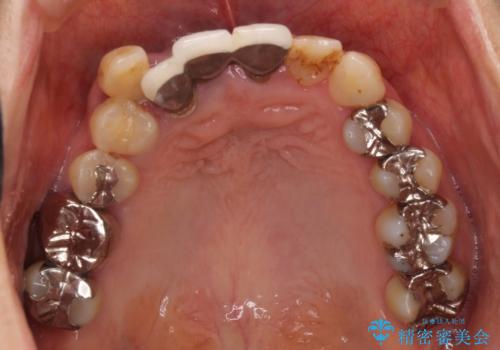

矯正を併用した前歯のセラミックブリッジ治療

- 上顎前歯をきれいにしたいとのことで来院されました。

レントゲンを撮影すると保存が難しい歯がありました。

またがたつきの度合いから歯を1本抜歯して矯正治療を行いセラミックブリッジを装着することで、審美的・機能的改善を行う計画としました。

治療の順序は

①保存不可の歯の抜歯・根管治療

②矯正治療

③セラミックの装着

という流れで行いました。

1年程度の治療期間が必要となりましたが、仕上がりには患者様に満足していただけました。